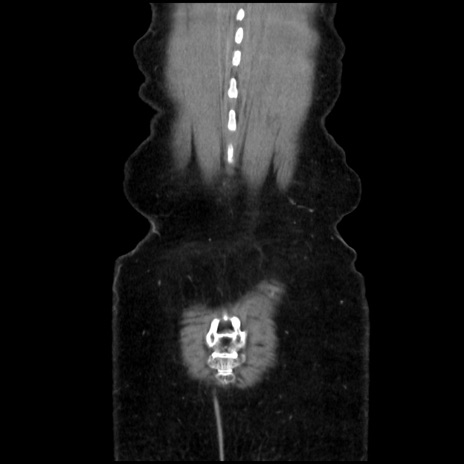

横断像

矢状断像